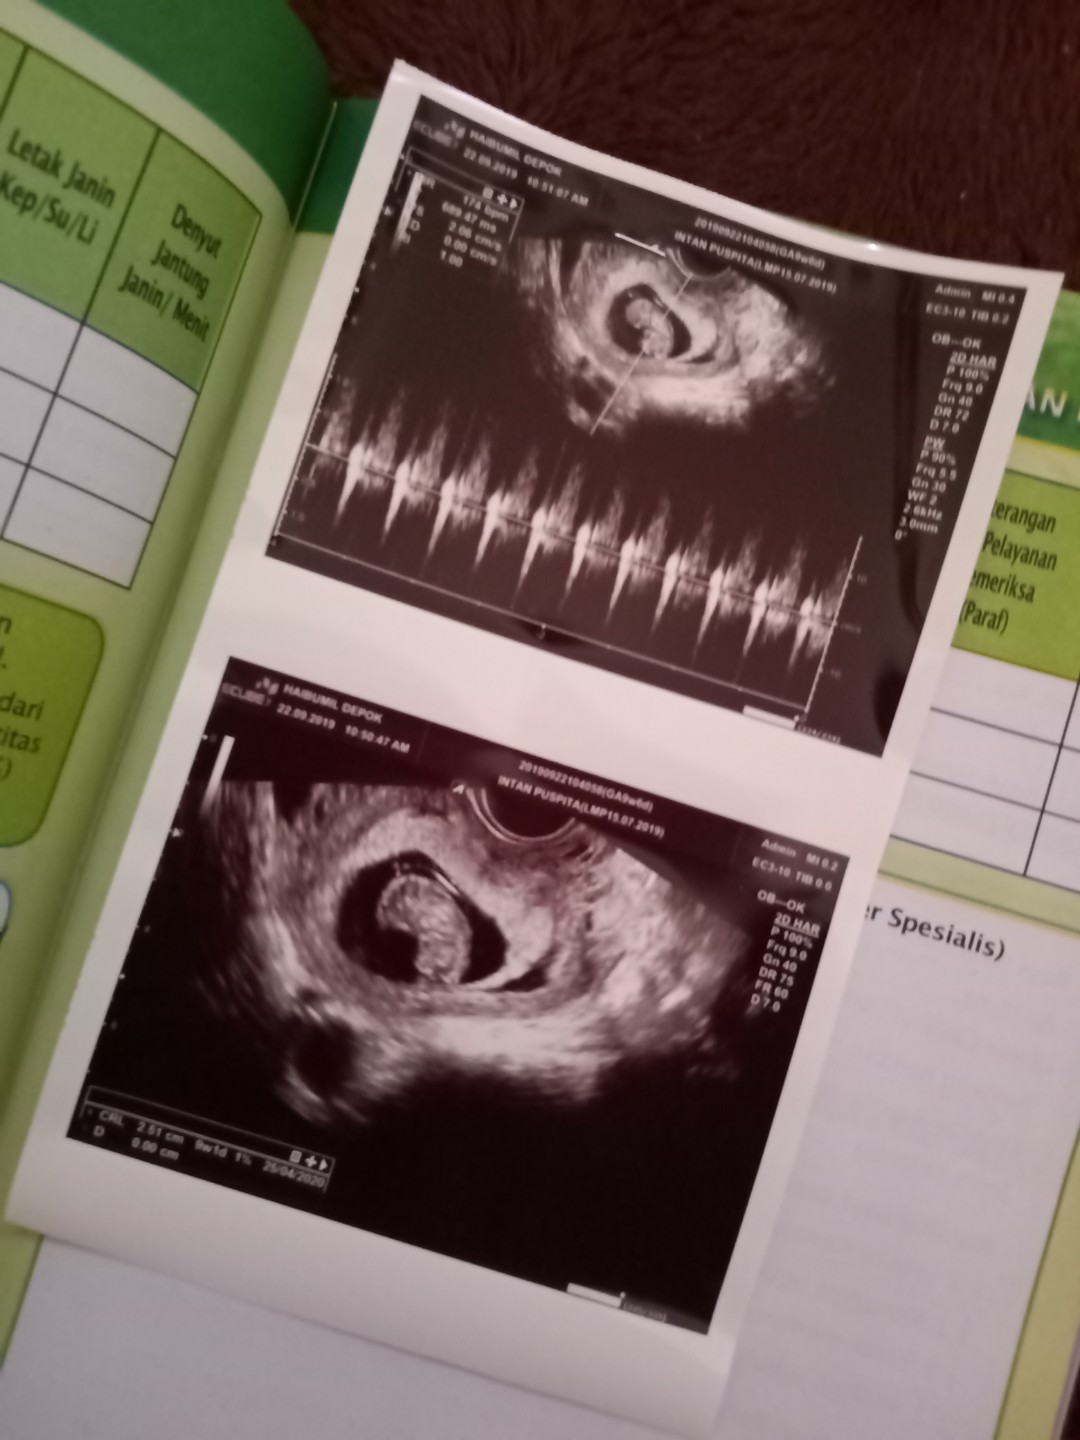

Sya pas usg 10w0d